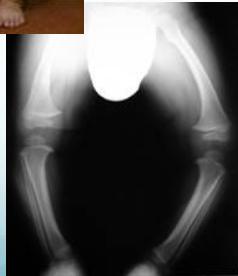

- Rickets

Rickets

Rickets - Improves with time